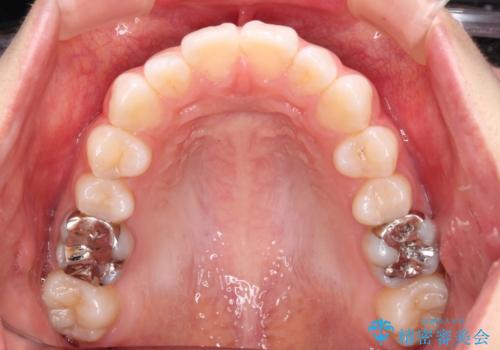

- 前歯の出っ歯と口元の閉じにくさを気にして来院された患者様です。

口元を積極的に引っ込めるために、上下左右の小臼歯4本を抜歯することとしました。

4本の歯を抜歯したことで、飛び出していた口元が引っ込み、横顔が大きく改善されました。